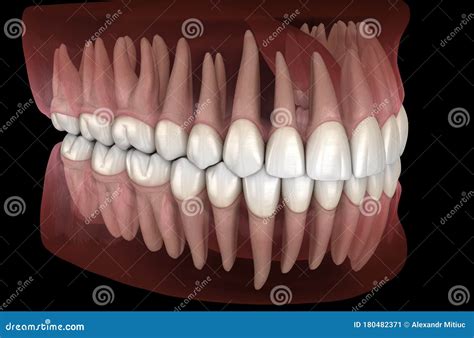

Teeth Contains the sockets for the upper teeth Contains the sockets for the lower teeth

These differences highlight the unique roles that the maxilla and mandible play in the structure and function of the facial skeleton. The maxilla is more involved in the formation of the facial bones and the separation of the oral and nasal cavities, while the mandible is crucial for the movement of the lower jaw and the process of chewing.

The maxilla and mandible have distinct functions that are essential for various physiological processes. The maxilla plays a crucial role in the formation of the facial skeleton and the separation of the oral and nasal cavities. It also provides attachment sites for various facial muscles and contains the sockets for the upper teeth. The mandible, on the other hand, is essential for the movement of the lower jaw and the process of chewing. It provides attachment sites for the muscles of mastication and contains the sockets for the lower teeth.

One of the most important developmental aspects of the maxilla and mandible is the eruption of the teeth. The teeth begin to erupt in infancy and continue to erupt throughout childhood and adolescence. The eruption of the teeth is a complex process that involves the growth and development of the alveolar processes of the maxilla and mandible. This process is essential for the proper alignment of the teeth and the development of a functional occlusion.